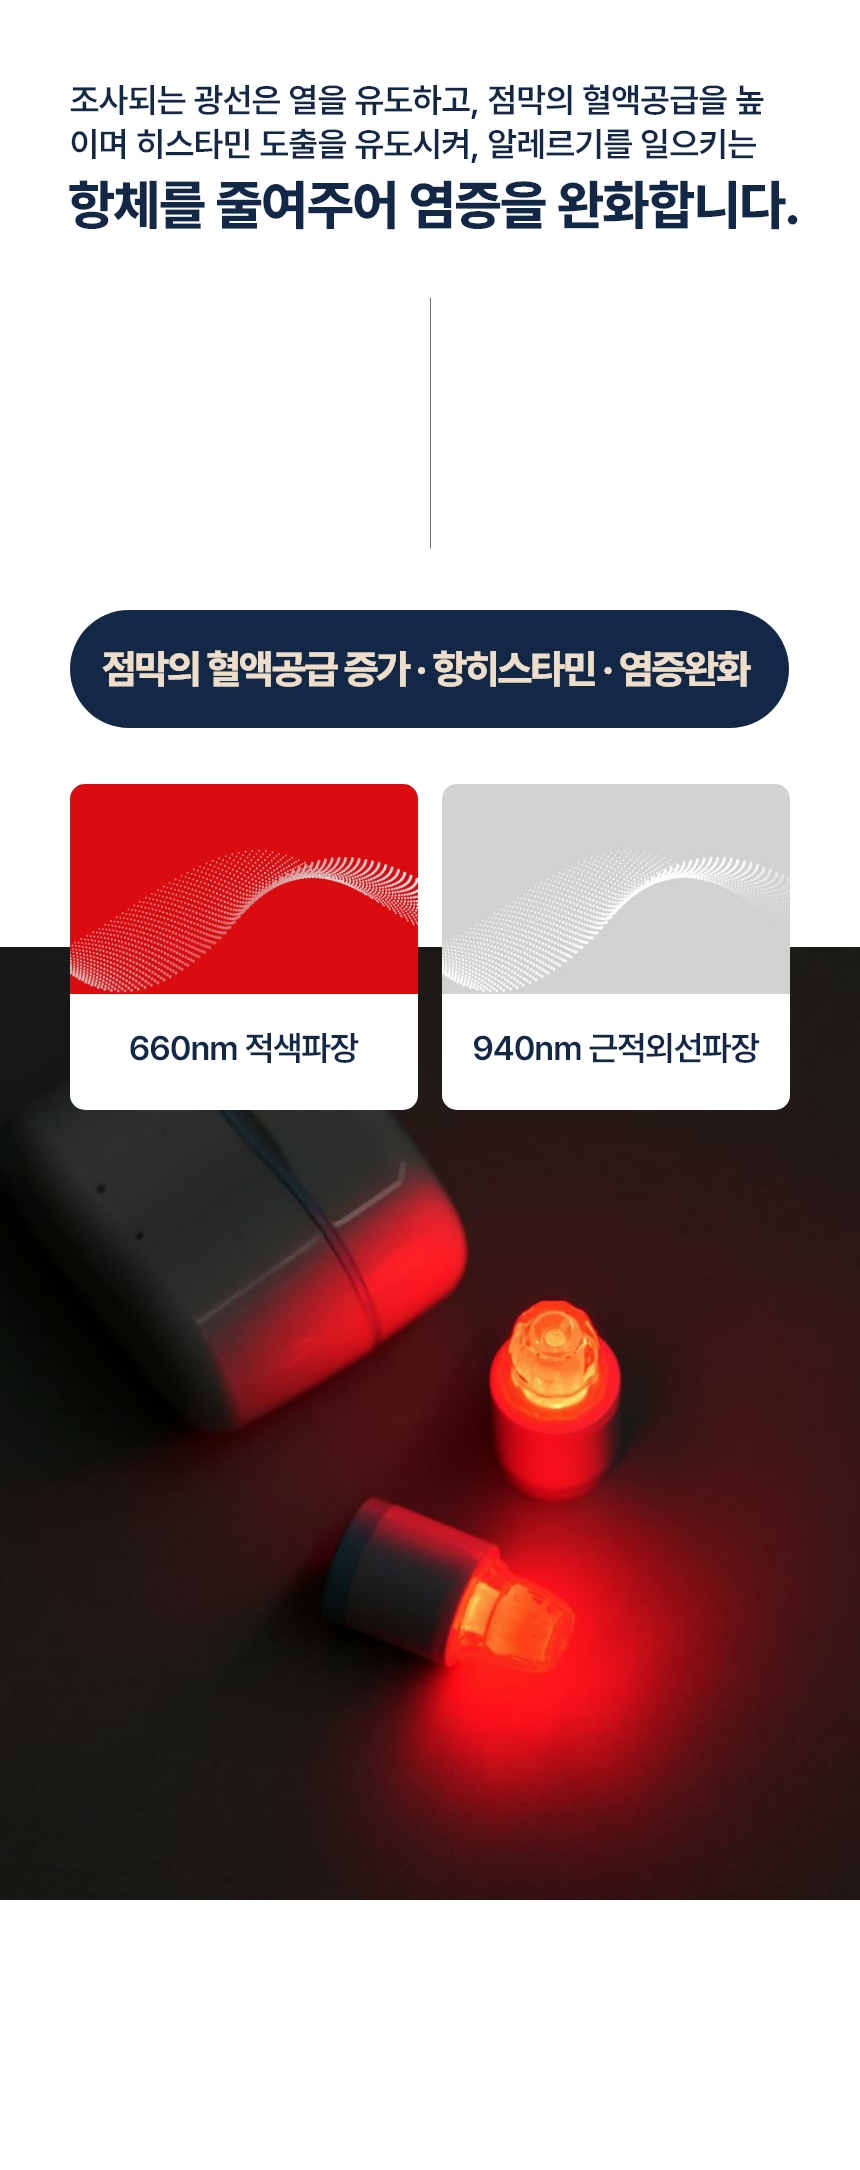

현재 특허 등록된 광 에미터 기술은 광 에미터(광가이드)를 이용해 LED를 외부에 두어 저항에 의한 발열을 콧속에 넣지않고, 비염에 도움이 되는 적색과 적외선 광선만 조사하는 방법입니다.

“LED는 빛도 나오지만 열도 나옵니다. 기기 끝에서 LED 빛이 나오면서 비강 점막을 건조시킨다는 부작용이 있었어요. 이를 개선하기 위해 무발열 광 에미터 기술을 적용했습니다. 광케이블처럼 LED 빛이 전파되는 통로를 만들어주는 방식이에요. 이비인후과에서 쓰는 광 치료기가 1세대, 기존 가정용 광치료기가 2세대라면 무 발열 광에미터 기술은 3세대라고 할 수 있죠.”